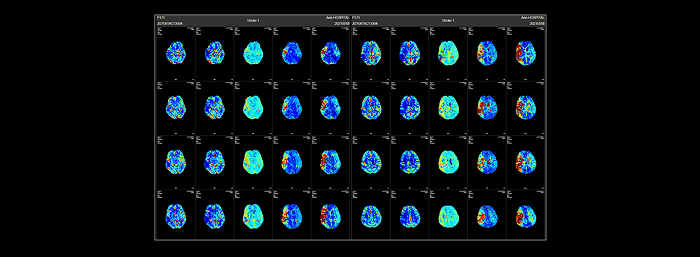

联影智能CTP脑灌注智能分析系统可自动重建灌注参数图(CBV、CBF、MTT、TTP、Tmax)与tMIP图像,精准定位与定量分析低灌注区、核心梗死区及错配(Mismatch)区域,可对CBV、CBF、Tmax进行多阈值分析,支持15个脑区自动分割并提供异常脑区分析,自动生成智能报告,支持智能胶片打印与归档,辅助医生多方位评估患者脑血流灌注情况,精高效诊疗。

联影智能CTP脑灌注分析系统能够定量地分析出核心梗死区、低灌注区与错配区,还能够提供CBF、CBV、Tmax等多参数、多阈值分析,以充足的量化信息为辅助医生全方位精准评估脑血流灌注情况,为患者提供更好的治疗决策。